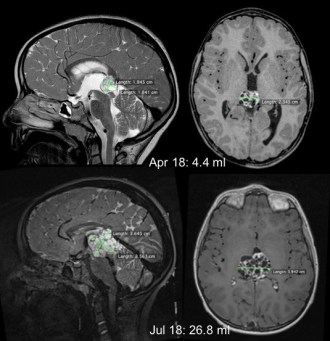

growing teratoma syndrome

dans de rares cas, les marqueurs se normalisent, alors que le volume tumoral augmente : ceci signe l’existence d’une composante tératomateuse (growing teratoma syndrome) cf. ci-contre. il est alors nécessaire d’en réaliser l’exérèse lorsqu’elle est possible.